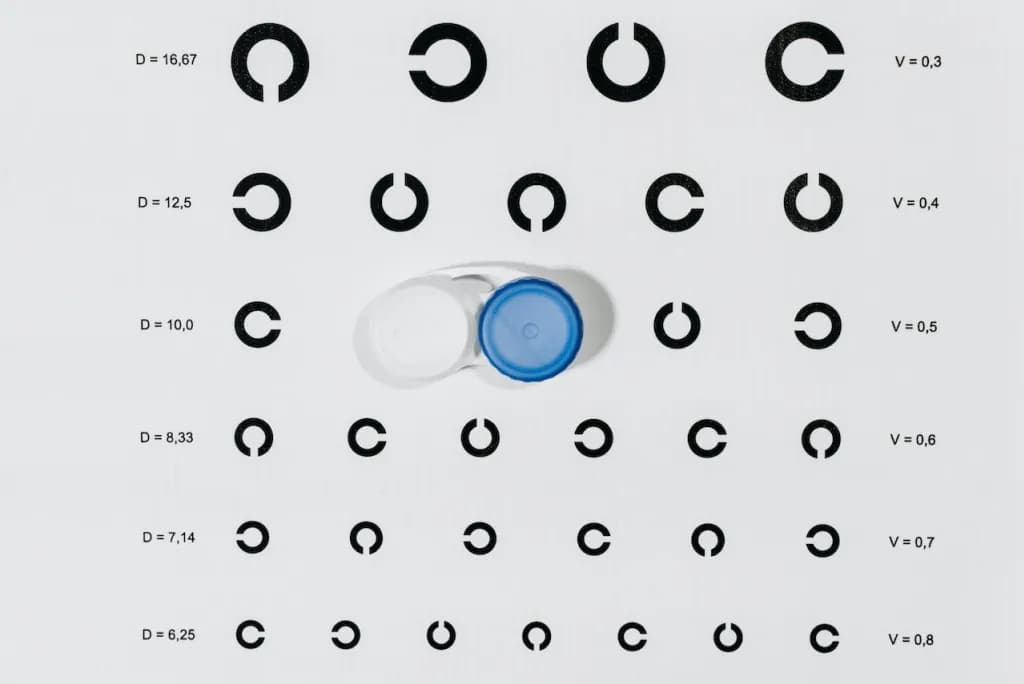

Szkła kontaktowe

Czym jest krzywizna soczewki i dlaczego ma kluczowe znaczenie dla oczu

Dowiedz się czym jest krzywizna soczewki i jak wpływa na komfort noszenia soczewek kontaktowych. Poznaj prawidłowe wartości i znaczenie tego parametru dla zdrowia Twoich oczu.